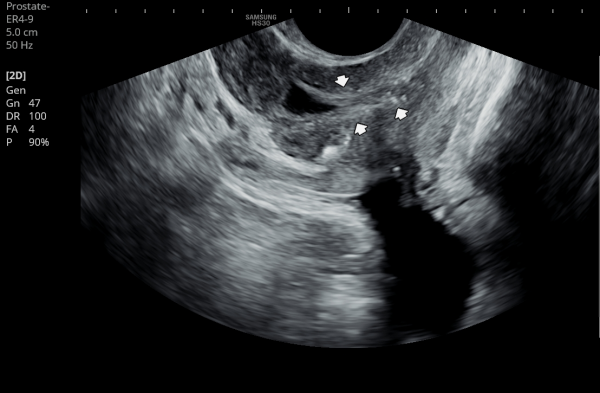

내원 첫 당일 경직장 전립선 초음파 검사상 사정관 입구의 결석들과 사정관 낭종이 관찰되는 사진입니다.(NIH:24)

On the initial transrectal prostate ultrasound, the image shows the presence of calcifications (stones) at the opening of the ejaculatory duct as well as a cystic lesion within the ejaculatory duct (ejaculatory duct cyst).(NIH:24)

주 2회 14주 동안 전립선과 정낭, 사정관과 정관등의 표적 치료후 사정관의 낭종등이 치료 되고 있는 경직장 전립선 초음파 검사 자료 입니다.(NIH:13)

This transrectal prostate ultrasound image shows improvement of an ejaculatory duct cyst after targeted treatment of the prostate, seminal vesicles, ejaculatory ducts, and vas deferens.

The treatment was performed twice a week over a period of 14 weeks. As a result, the previously noted cyst in the ejaculatory duct is gradually resolving, indicating improved drainage and recovery of normal ductal circulation.(NIH:13)

For the patient, this means that small stones and a cyst are blocking the natural passage where semen normally flows. These findings can explain symptoms such as pelvic pain, difficulty with ejaculation, blood in semen, or infertility.

Treatment may involve addressing these blockages to restore normal flow and relieve associated symptoms.

내원 당일 경직정 전립선 정면 사진상 전립선내의 이행구역과 중심 구역 등에 광법위하게 관찰되는 결석과 우측 전립선 부위의 결석이 더 진행된 사진입니다.(NIH:24)

On the transrectal ultrasound image taken on the day of your visit, we can see that multiple stones are widely distributed within the transition zone and central zone of the prostate.

In addition, the image shows that the stones on the right side of the prostate are more advanced and progressed compared with other areas.(NIH:24)

주 2회 14주 동안 전립선과 사정관, 정낭 그리고 정관등의 표적 치료후 전립선의 결석이 치료되고 있는 경직장 전립선 초음파 사진입니다.(NIH:13)

This transrectal prostate ultrasound image shows improvement of prostatic stones after targeted treatment of the prostate, ejaculatory ducts, seminal vesicles, and vas deferens.

The treatment was performed twice a week for 14 weeks, and the previously observed prostatic calcifications are gradually resolving, suggesting improved drainage and recovery of prostate function.(NIH:13)